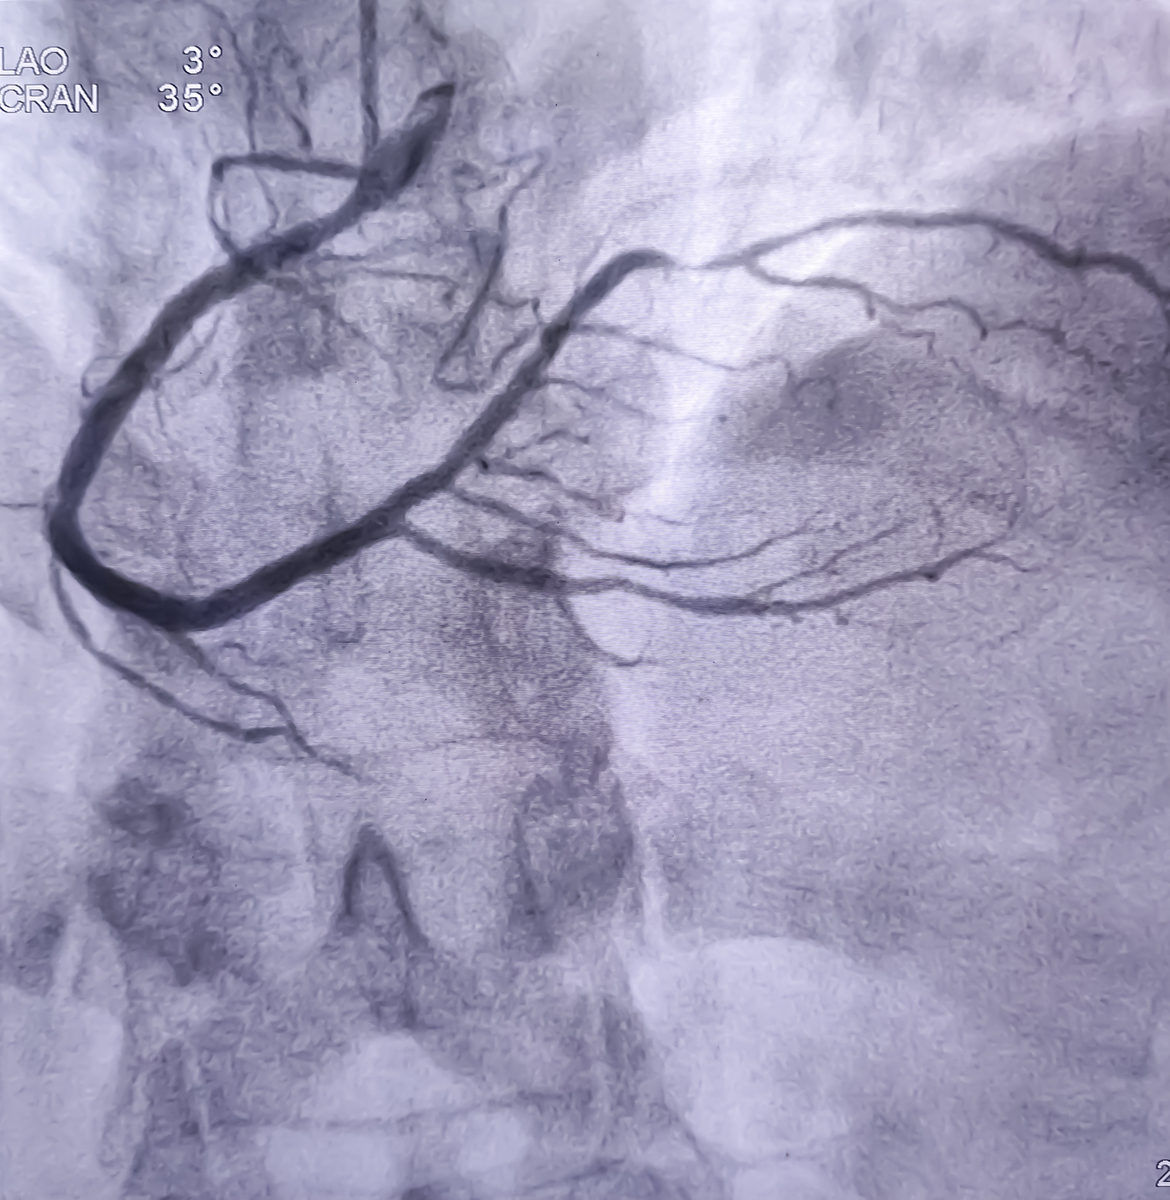

颈动脉超声造影(Carotid CEUS)是一种推荐的诊断方法,由于其操作简单便捷、实时监测、非侵入性、无辐射暴露、非肾毒性和床边检查的特点,在临床应用中备受青睐。